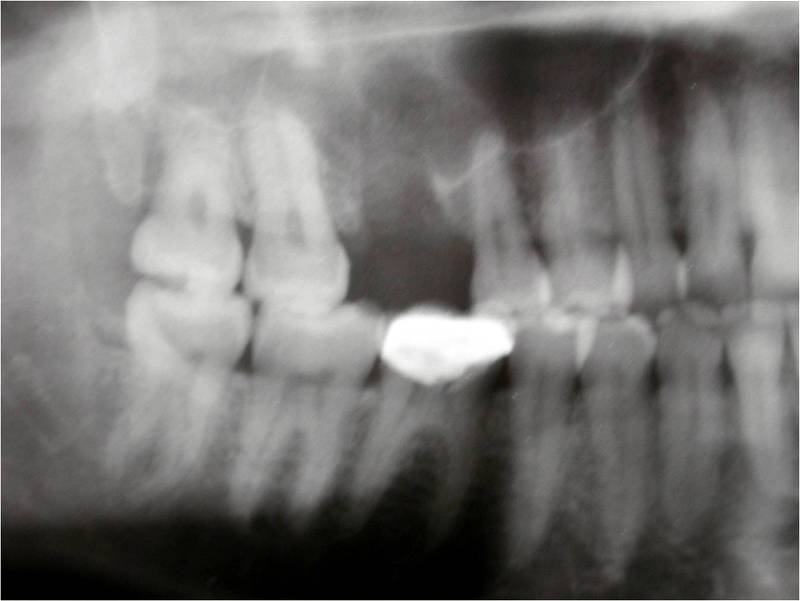

Root Canal Material In The Jaw